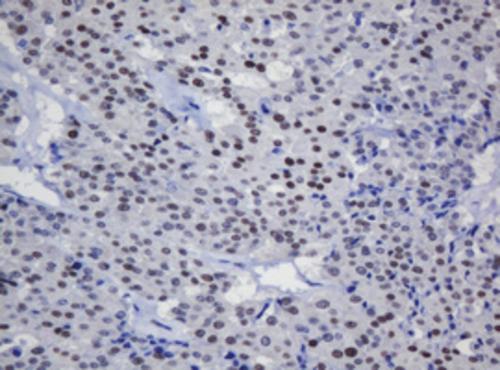

Immunohistochemical staining of paraffin-embedded Human prostate tissue within the normal limits using anti-TRMT2A mouse monoclonal antibody. (Heat-induced epitope retrieval by 10mM citric buffer, pH6.0, 120°C for 3min, BD-PE4529)

Immunohistochemical staining of paraffin-embedded Carcinoma of Human thyroid tissue using anti-TRMT2A mouse monoclonal antibody. (Heat-induced epitope retrieval by 10mM citric buffer, pH6.0, 120°C for 3min, BD-PE4529)